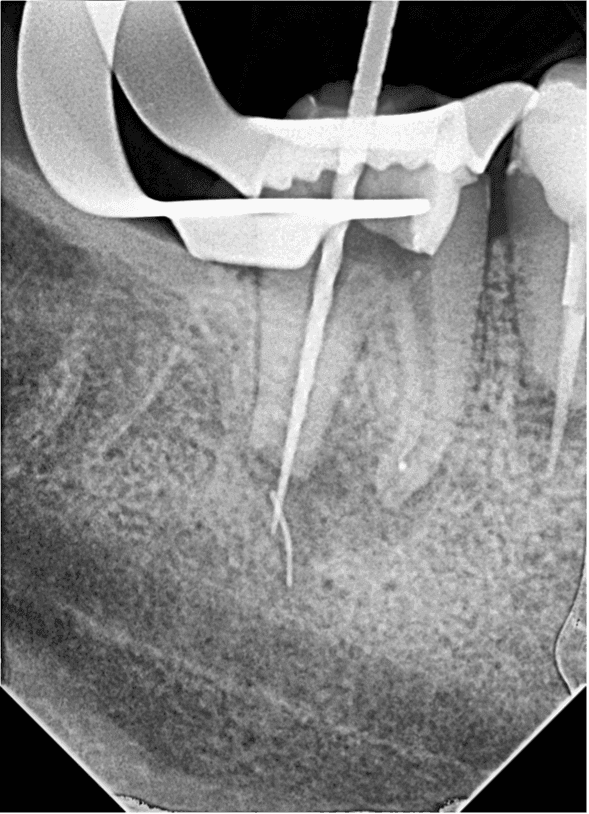

29 yaşındaki sağlıklı erkek hasta kök kanalındaki kırık eğe nedeni ile kliniğimize başvurdu. Yapılan radyografik muayenede distal kanalda apikalden taşkın guta ve kırık alet olduğu tespit edildi (RESİM 1).

RESİM 1: Apikalden taşkın eğe ve guta